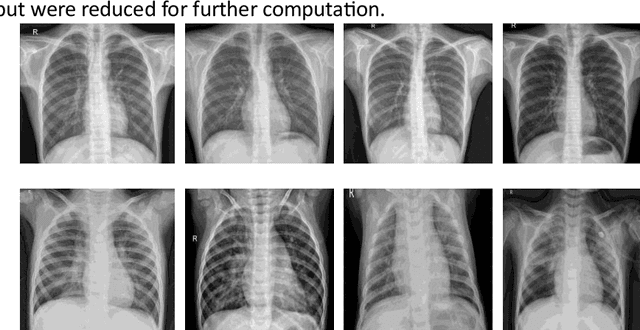

Abstract:Diagnosing lung inflammation, particularly pneumonia, is of paramount importance for effectively treating and managing the disease. Pneumonia is a common respiratory infection caused by bacteria, viruses, or fungi and can indiscriminately affect people of all ages. As highlighted by the World Health Organization (WHO), this prevalent disease tragically accounts for a substantial 15% of global mortality in children under five years of age. This article presents a comparative study of the Inception-ResNet deep learning model's performance in diagnosing pneumonia from chest radiographs. The study leverages Mendeleys chest X-ray images dataset, which contains 5856 2D images, including both Viral and Bacterial Pneumonia X-ray images. The Inception-ResNet model is compared with seven other state-of-the-art convolutional neural networks (CNNs), and the experimental results demonstrate the Inception-ResNet model's superiority in extracting essential features and saving computation runtime. Furthermore, we examine the impact of transfer learning with fine-tuning in improving the performance of deep convolutional models. This study provides valuable insights into using deep learning models for pneumonia diagnosis and highlights the potential of the Inception-ResNet model in this field. In classification accuracy, Inception-ResNet-V2 showed superior performance compared to other models, including ResNet152V2, MobileNet-V3 (Large and Small), EfficientNetV2 (Large and Small), InceptionV3, and NASNet-Mobile, with substantial margins. It outperformed them by 2.6%, 6.5%, 7.1%, 13%, 16.1%, 3.9%, and 1.6%, respectively, demonstrating its significant advantage in accurate classification.